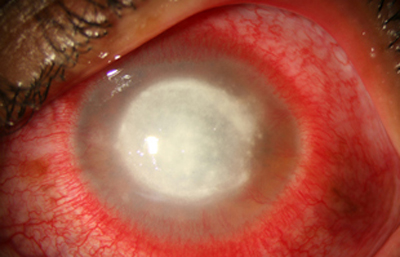

Superficie corneal irregular y grisácea, (Fig. 1, 2) con opácidades granulares en parche y formación de líneas epiteliales elevadas de aspecto granular (Fig. 3), que pueden arborizar dando imágenes de pseudodendritas. Opacidades superficiales satélites. (Figura 4) Inyección ciliar. Ulceración epitelial variante. (Figura 5).

Fig. 1 Síntomas de 15 días evolución